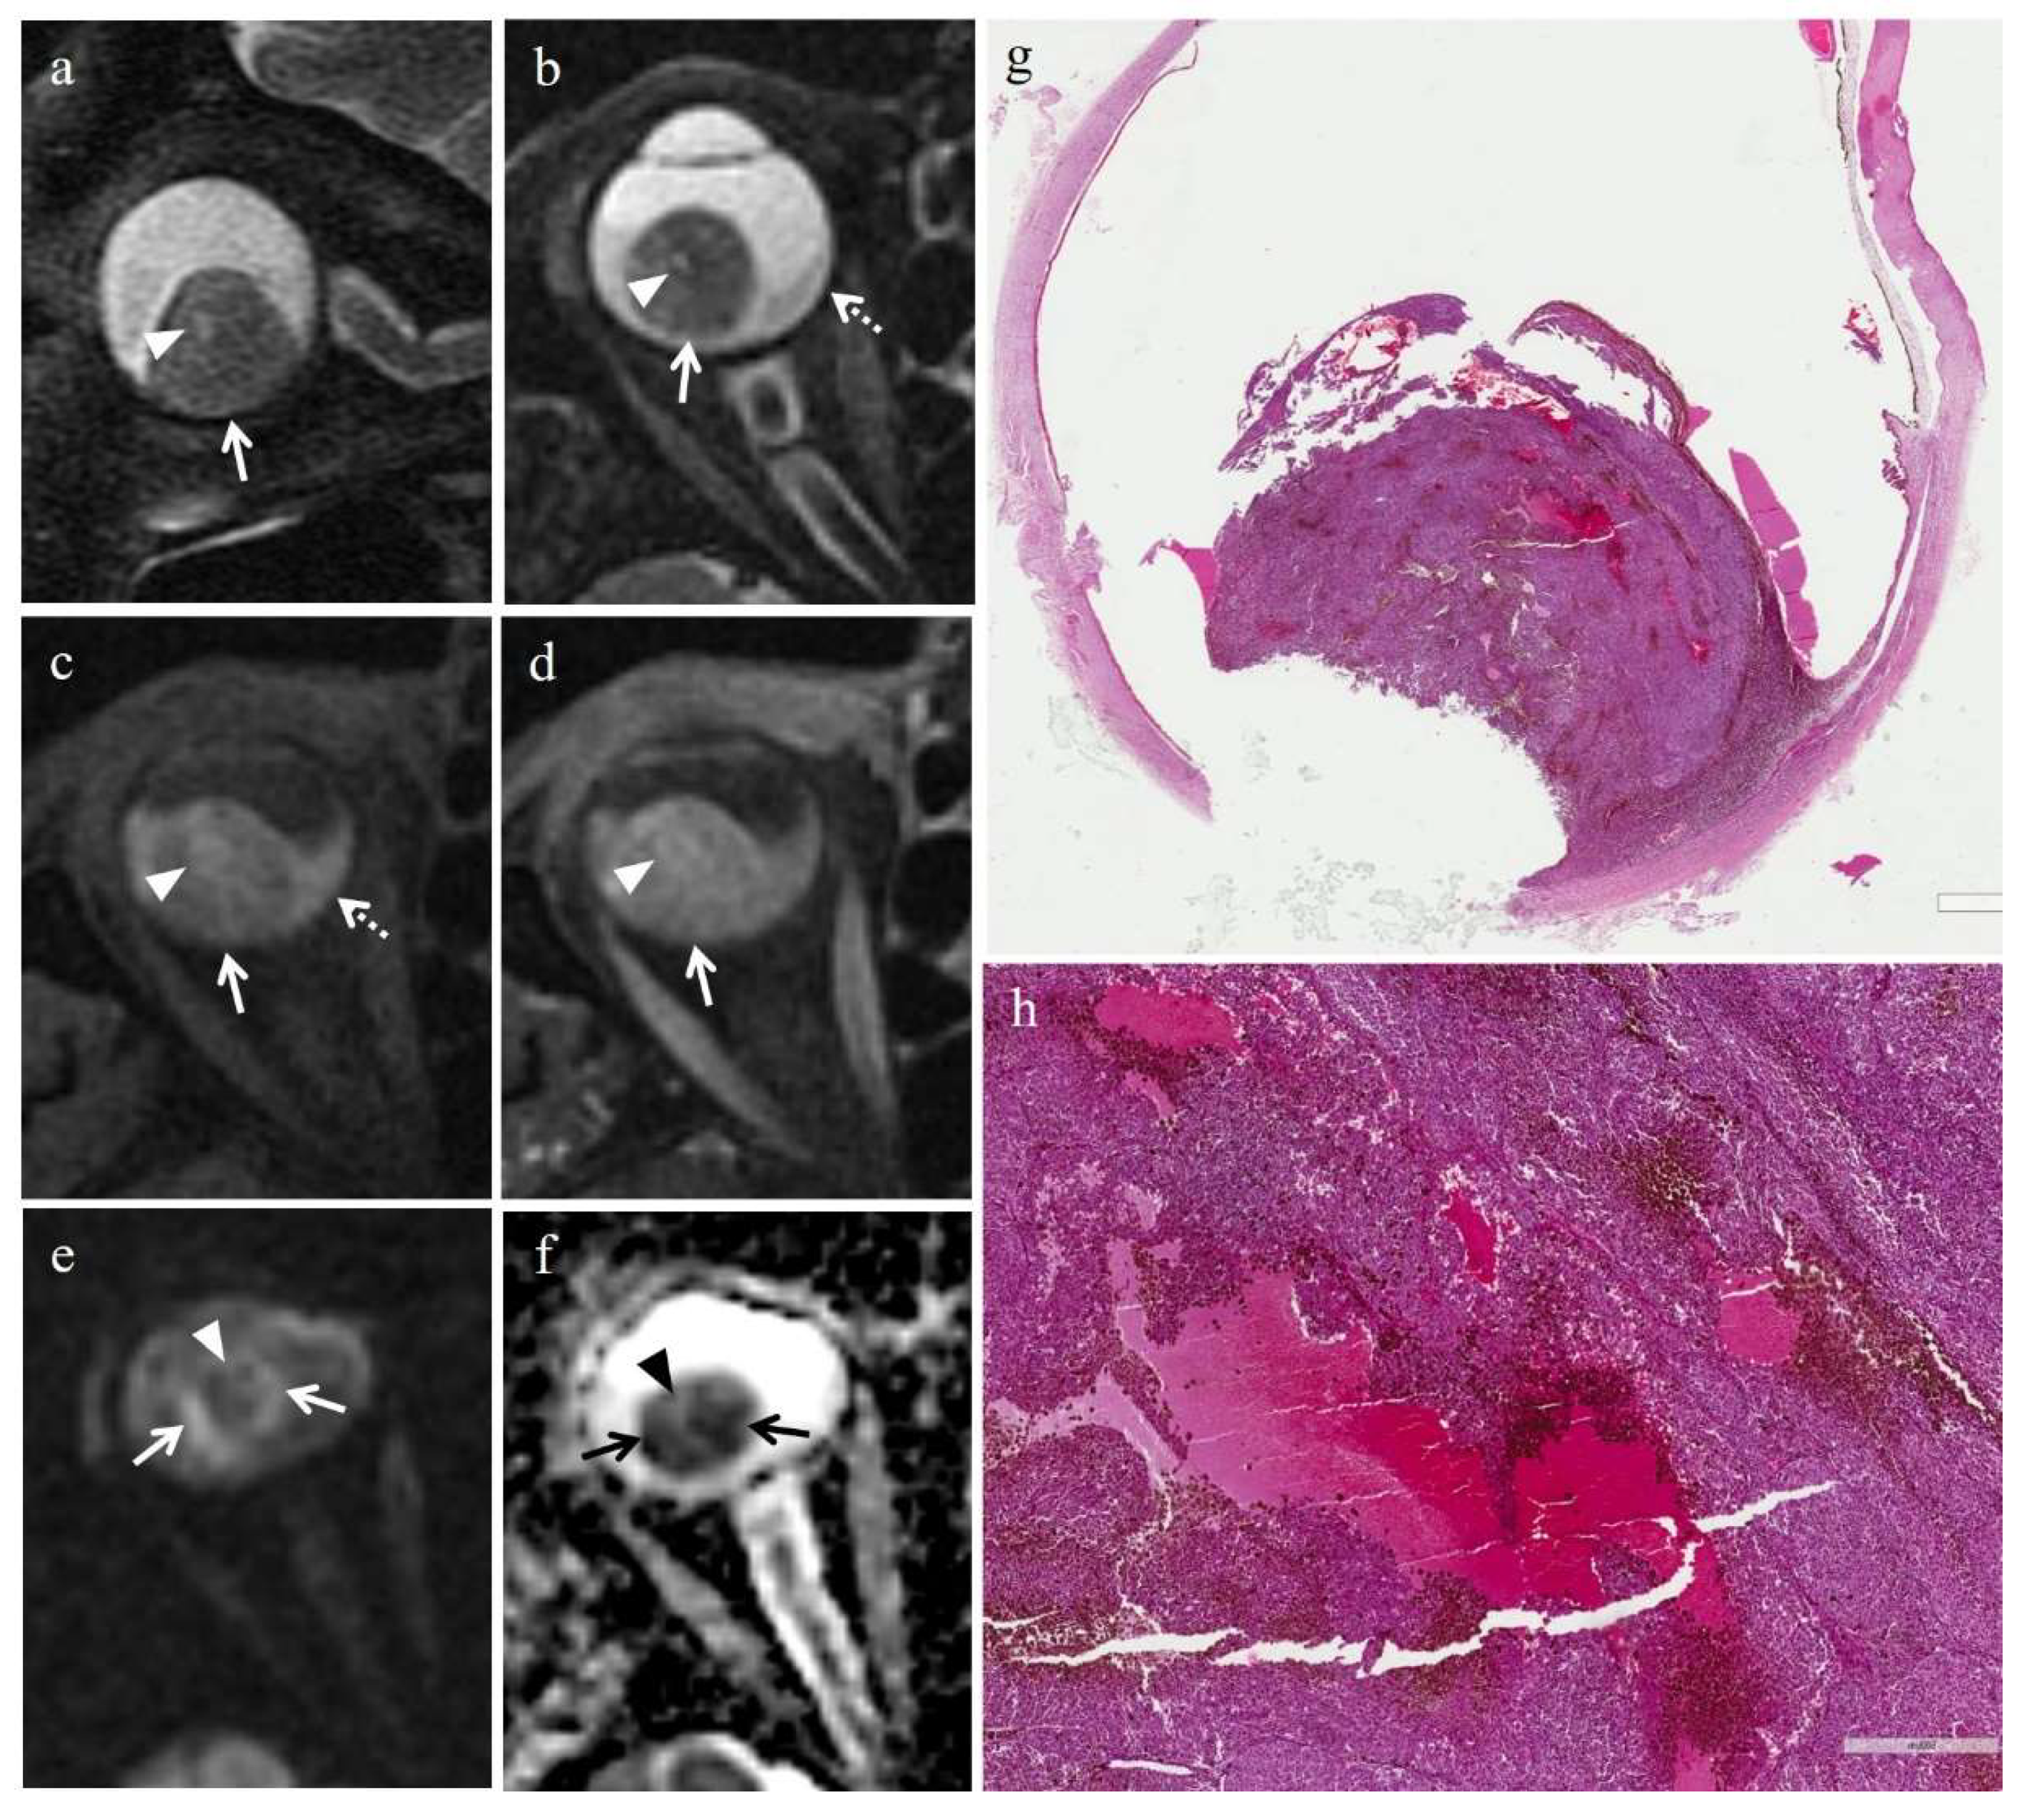

3.2.1. Histopathologic Findings in the Irradiated Group

3.3.1. MRI Findings in the Irradiated Group

| Patient | Histologic Type | Degree of Pigmentation | Degree of Necrosis | Necrotic Pattern |

|---|---|---|---|---|

| 1 | Necrosis without viable tumor tissue | - | Grade III | Sharply demarcated tumor necrosis |

| 2 | Spindle cell | Pigmented | Grade I | Sharply demarcated tumor necrosis |

| 3 | Epithelioid cell | Pigmented | Grade II | Sharply demarcated tumor necrosis |

| 4 | Spindle cell | Pigmented | Grade III | Sharply demarcated tumor necrosis |

| 5 | Mixed cell type | Poorly pigmented | Grade I | Multiple foci- hemorrhagic/coagulative-type |

| 6 | Mixed cell type | Poorly pigmented | Grade III | Sharply demarcated tumor necrosis |

| 7 | Spindle cell | Poorly pigmented | Grade III | Sharply demarcated tumor necrosis |

| MR Finding | T2 | T1 | Gd-T1 | DWI |

| Radiation-induced necrosis | ![]() Low signal | ![]() High signal | ![]() No enhancement | ![]() Low signal |

| Radiation-induced necrosis with viable tumor tissue | ![]() M RIN | ![]() M RIN | ![]() M RIN | ![]() M RIN |

| Hemorrhagic necrosis in untreated melanoma | ![]() High signal | ![]() Low signal | ![]() No enhancement | ![]() Low signal |

low signal;

high signal;

no enhancement; M: melanoma; RIN: radiation induced necrosis.| Patient | T2 | T1 | Gd-T1 | DWI | ADC × 10−3 mm2/s ** |

|---|---|---|---|---|---|

| 1 | Hypointense | Hyperintense | No enhancement | No restriction | - |

| 3 | Hypointense | Hyperintense | No enhancement | No restriction | 0.84 |

| 4 | Hypointense | Hyperintense | No enhancement | No restriction | - |

| 5 | Hyperintense | Hypointense | No enhancement | No restriction | 0.67 |

| 6 | Hypointense | Hyperintense | No enhancement | No restriction | - |

| 7 | Hypointense | Hyperintense | No enhancement | No restriction | 0.86 |